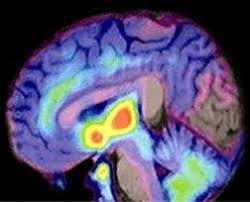

Las empresas y los Institutos Nacionales de Salud de Estados Unidos compartirán los científicos, los tejidos y las muestras de sangre, y los datos, para unificar objetivos en la búsqueda de nuevos medicamentos para enfermedades como el alzhéimer la diabetes tipo 2, la artritis reumatoide y el lupus.

La cooperación denominada The Accelerating Medicines Partnership,(AMP) tendrá un coste de unos 320 millones de dolares, de los cuales 135 estarán destinados a la investigación del alzhéimer, según ha declarado recientemente el congresista estadounidense Chaka Fattah y en ella participaran la mayor parte de las principales farmacéuticas como Bristol-Myers Squibb Co, Johnson & Johnsons ,GlaxoSmithKline, Takeda Pharmaceuticals y Sanofi.